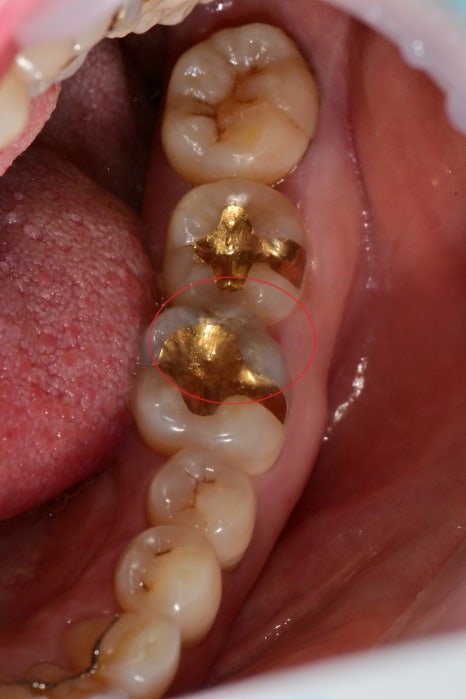

오늘 설명할 치료 부위는 과거의 금 인레이로 치료 받은 부위가 금이 가있고, 주변 하방에 2차 우식이 생겼습니다.

과거 금 인레이를 제거 후 하방의 충치들도 모두 제거 한 사진입니다.

1번 사진은 아직 과거의 하방 베이스를 이루는 공간을 채운 수복물을 제거 하기 전입니다.

깨끗하게 제거후 확인해보니 치아 원심측 부위부터 가운데까지 금이 진행한걸 볼수 있었습니다.